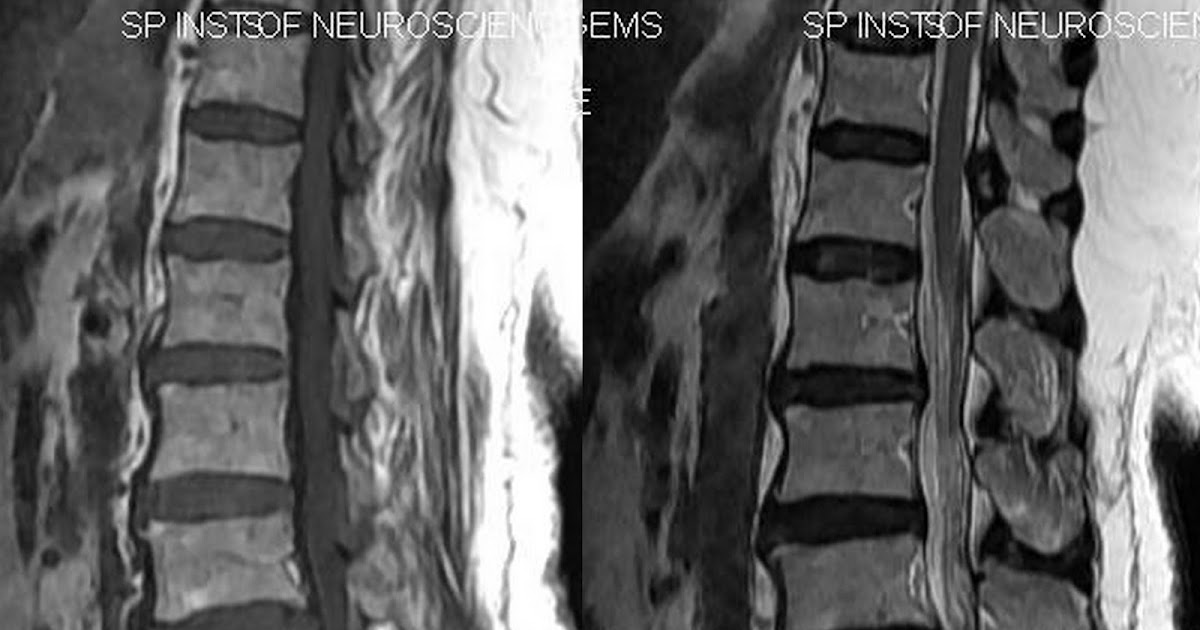

MRI sagittal image with white arrows at level of disc involvement in 4a Causes Of Vacuum Disc Phenomenon Vacuum phenomenon (vp) is defined as air within a joint. Vacuum disc phenomenon is the presence of gas in degenerated spinal discs, which can cause pain, instability, and nerve compression. Learn about the causes, symptoms,. Intervertebral vacuum phenomenon (ivp) is usually observed in advanced degeneration. Many pathologies are associated with vp, mainly degenerative. Vacuum disc phenomenon is seen frequently with. Causes Of Vacuum Disc Phenomenon.